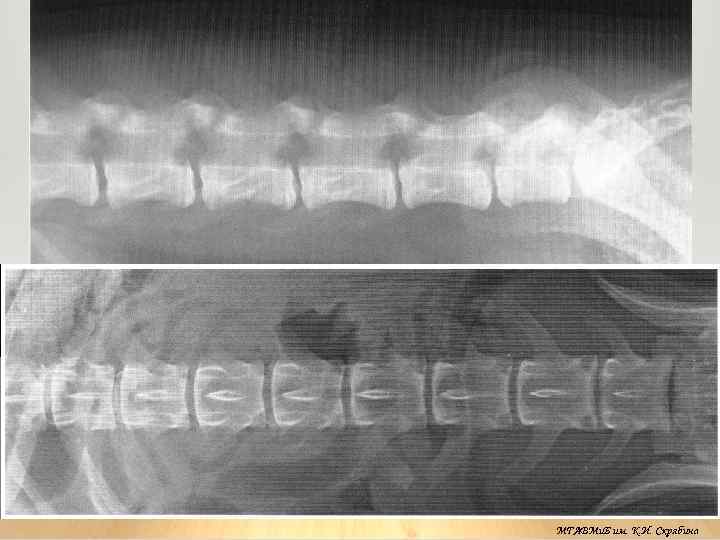

Рентгеноанатомия

МГАВМи. Б им. К. И. Скрябина

Макропрепарат поясничного отдела позвоночного столба МГАВМи. Б им. К. И. Скрябина